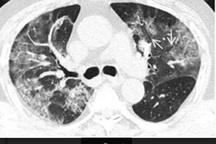

Lãnh đạo Bệnh viện Trung ương Huế cơ sở 2 cho biết còn có BN 438 Đoàn Ngọc T. (56 tuổi) có kết quả xét nghiệm Covid-19 âm tính 2 lần. Tuy nhiên bệnh nhân này đang trong tình trạng nặng nguy kịch, thở máy với bệnh lý nền viêm phổi đa đề kháng, suy hô hấp, u ác tính niệu quản đã phẫu thuật, tăng huyết áp, COPD, suy kiệt. Các bác sĩ đang nỗ lực, tập trung nguồn lực để cứu sống bệnh nhân này.